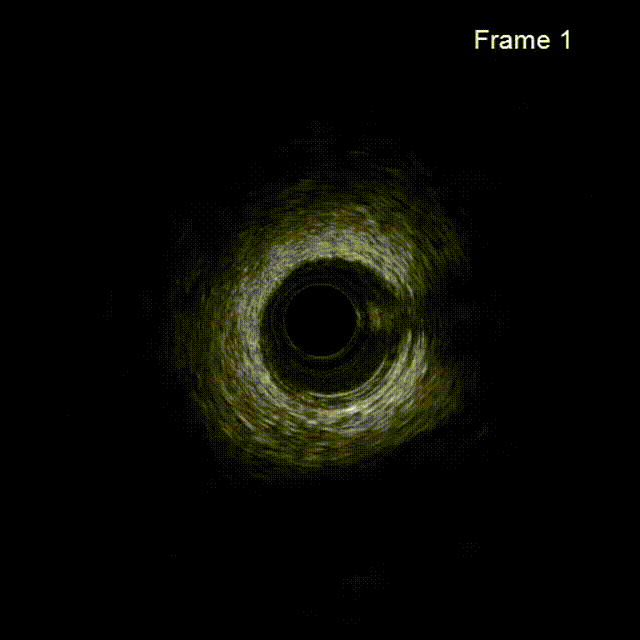

依次用Pinoeer 2.0mm x 15mm、Pinoeer 2.5mm x 15mm球囊至病变处反复扩张,送入Marvel导丝至D1远段做保护,LAD行IVUS检查。

IVUS检查示:可见导丝全程走行与血管真腔,近中段重度纤维增生斑块伴局部钙化,远段血管床废用性萎缩。

术后行IVUS检查示:支架定位贴壁扩张良好,LAD开口MSA:7.43mm2。